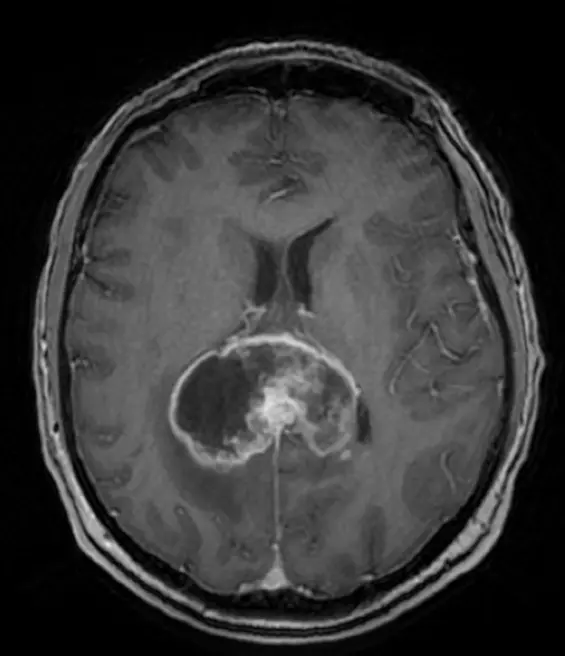

Ring-enhancing lesion: A ring-enhancing lesion appears as a bright rim surrounding a darker centre after contrast dye is administered during an MRI or CT scan18. The ring is due to contrast uptake at the edge of the lesion, often raising concern for aggressive or infectious processes.

Butterfly lesion: A butterfly lesion refers to a mass that crosses the midline of the brain through the corpus callosum, giving it a butterfly appearance on imaging24. This is common in glioblastomas.

30. Wang M, Wang Z, Ren P, et al. Meningioma with ring enhancement on MRI: a rare case report. BMC Med Imaging. 2021;21:22. doi:10.1186/s12880-021-00555-x